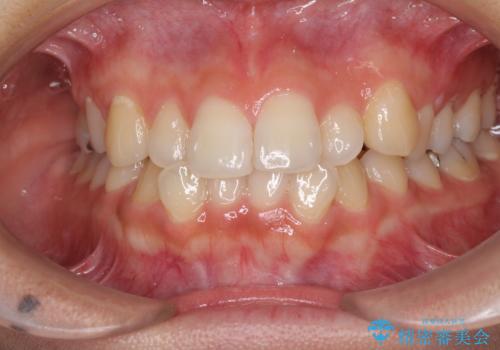

前歯の突出感とデコボコ インビザラインで改善

- 上下前歯のデコボコを気にして来院された患者様です。

インビザラインによる上下歯列の側方拡大と後方移動、IPR(歯と歯の間を削る)にるスペースの獲得により歯列を整えることとしました。